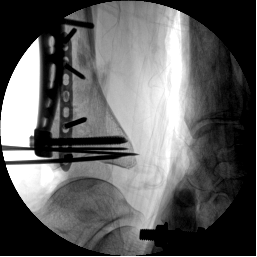

2.CO接骨機器人持續(xù)牽引維持復(fù)位,選擇前外側(cè)切口對前外側(cè)骨塊進(jìn)行撬撥復(fù)位,并用克氏針進(jìn)行臨時固定。C臂透視復(fù)位滿意,放置兩塊鋼板進(jìn)行固定。

3.在脛骨近端穿入一根克氏針,連接CO外固定架進(jìn)行固定,并外踝處穿入一根克氏針進(jìn)行固定。C臂透視位置滿意,縫合結(jié)束手術(shù)。